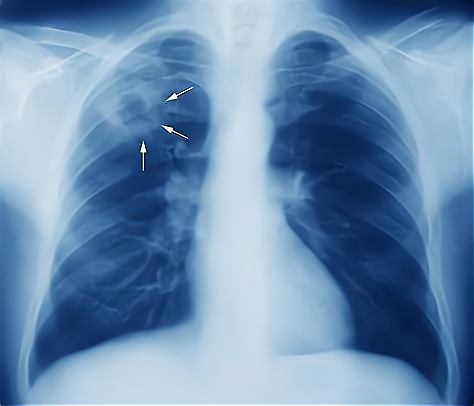

肺结核是由于肺部感染了结核杆菌引起的传染性疾病 , 通过空气、飞沫经呼吸道传染 。 如果有大量的结核菌反复吞入消化道 , 也可能导致肠结核和结核性腹膜炎 。 个别患者 , 结核杆菌可以大量进入血液 , 引起血行播散型肺结核 。 严重的还可以导致结核性脑膜炎等危及生命的疾病 。

有传染性的肺结核患者 , 比如空洞型肺结核患者 , 在咳嗽、打喷嚏、大声说话、唱歌的时候 , 痰液中的结核杆菌排放到空气中 , 其中比较大的颗粒 , 会很快掉落地面或者或者家具的表面 , 小的颗粒则漂浮在空气中细小的浮尘上 , 而其中只有直径小于五微米的颗粒 , 才可能被健康人吸入 。

这些带有结核杆菌的微小颗粒 , 不一定能够全部到达肺泡 , 有一些会被气管、支气管上的黏乎乎的痰液粘附 , 最终被健康人通过咳嗽排出体外 , 只有到达肺泡的结核分枝杆菌 , 才有可能最终导致肺部感染 , 也就是肺结核 。

人体的免疫系统中的一些细胞 , 如单核-巨噬细胞等 , 一般来说会把细菌这样的“异物”吞噬并消灭 。 所以 , 即使吸入含有结核杆菌的颗粒 , 也不代表一定会得肺结核 , 其中只有15%~20%的人 , 可能最终会发展成为肺结核患者 , 其余的也可能成为潜伏性的感染者 , 更多的人并无影响 。